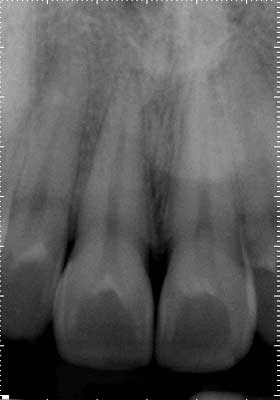

Exam: Teeth Nos. 2 through 5 responded normally to cold with no lingering and were asymptomatic to percussion, so the field of testing was expanded. Tooth No. 8 was nonresponsive to cold and heat. Both Nos. 7 and 8 were hypersensitive to percussion but had no restorative history, and the patient denied any history of trauma. There was no clinical evidence of an enamel defect associated with tooth No. 8. Radiographically, the apical and crestal bone was unremarkable around teeth Nos. 2 through 9. Teeth Nos. 3, 4, and 5 had significant restorative histories.Anterior preop

Pulpal diagnosis: Necrotic pulp No. 8

Periapical diagnosis: Symptomatic apical periodontitis